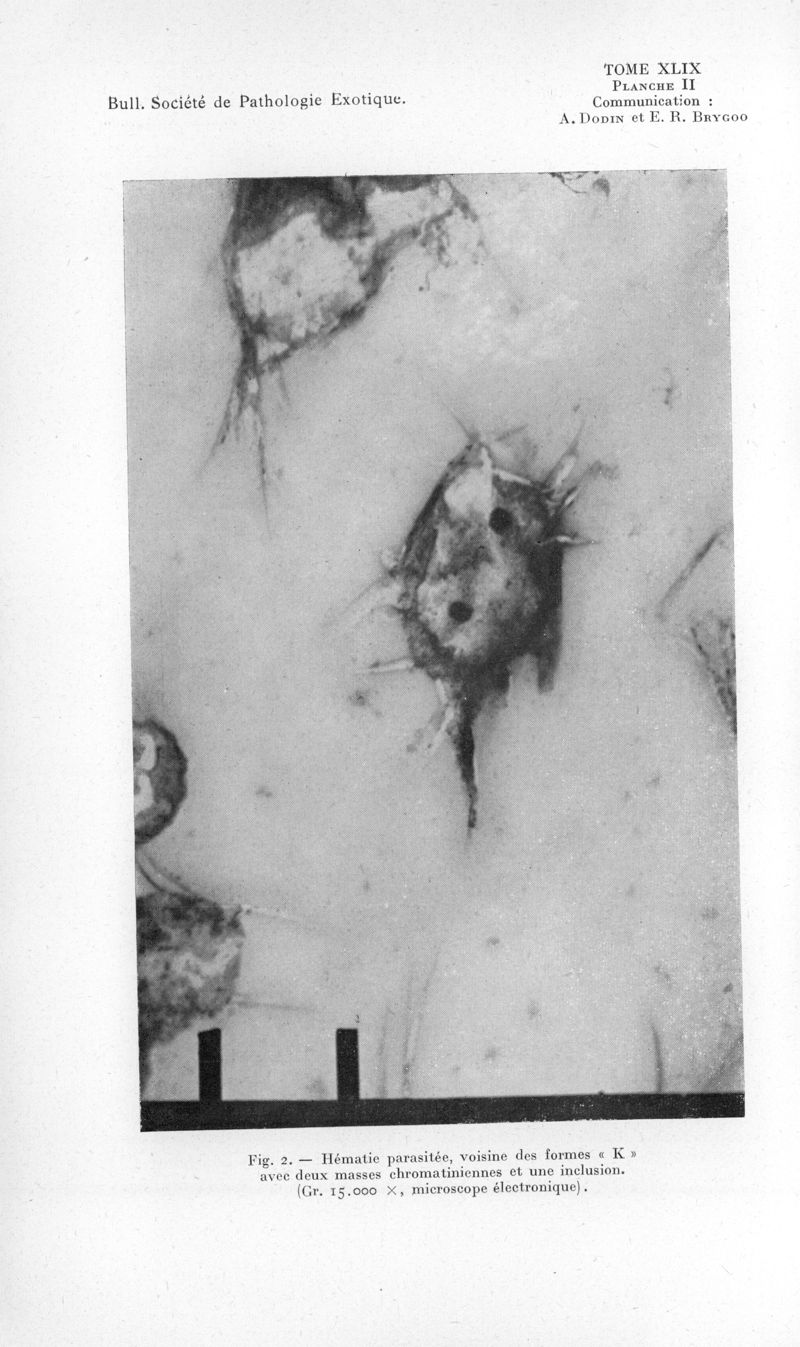

Bulletin de la Société de pathologie exotique et de ses filiales

1956, tome 49. - Paris : Masson, 1956.